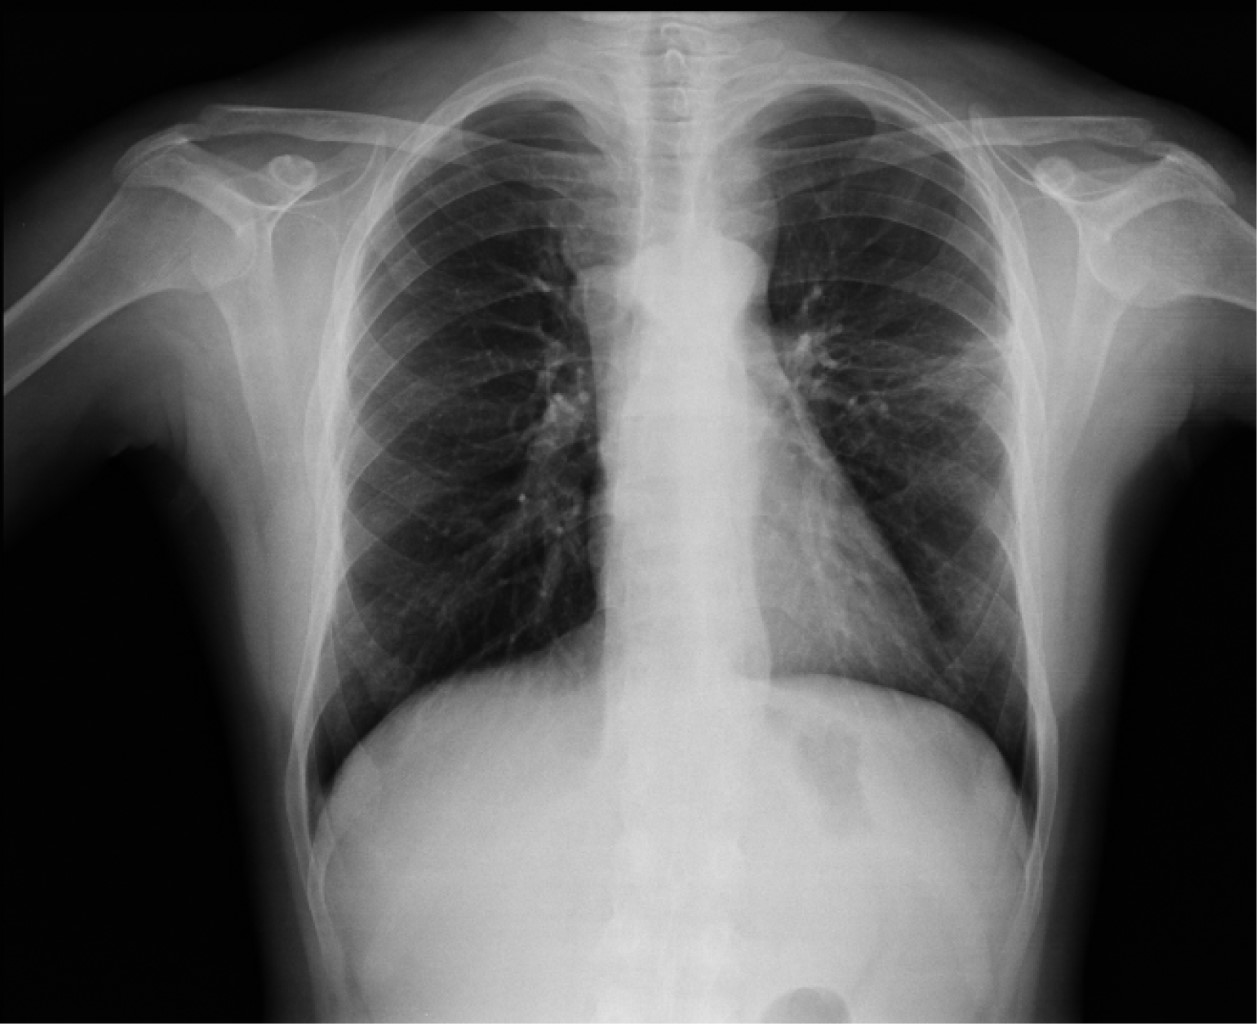

Mujer de 29 años con trasplante renal de donador fallecido en 2017. Con riesgo alto para CMV. Se dio inducción con basiliximab. Sin manejo profiláctico con valganciclovir. Inmunosupresión con micofenolato de mofetilo, prednisona y tacrolimus. Tres meses después ingresa por encontrar en consulta externa lesiones ulceradas en mejillas, además de carga viral de un millón de copias, por lo cual decide hospitalizarse. Documentándose además disfunción aguda de injerto, trombocitopenia de 95,000 plaquetas por µL, niveles de tacrolimus de 18 ng/mL. Se inicia manejo con valganciclovir y a las 48 horas presenta fiebre de 38 °C, tos seca, disnea, polipnea, motivo por el cual se solicita tomografía axial computarizada (TAC) de tórax que muestra imagen en vidrio despulido bilateral, engrosamiento pleural, zonas de atelectasia, lesión intercisural izquierda, de bordes deshilachados, aspecto de "lesión en erizo", imagen que sugiere aspergilosis pulmonar, (Figura 1) por lo cual se inicia manejo con voriconazol y al egreso virando a itraconazol. Se realiza fibrobroncoscopia y se reporta prueba de galactomanano positivo. Se mantuvo con manejo con valganciclovir por tres meses con posterior carga viral no detectada, así como itraconazol por un año con mejoría radiográfica y clínica y controles periódicos (Figura 2).

Figura 1